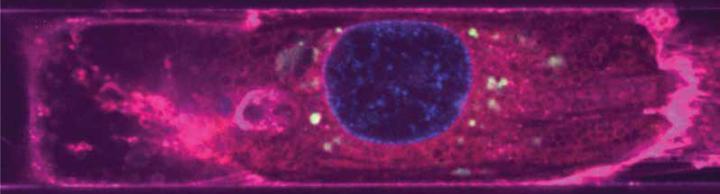

image: Endothelial-derived EVs (green) around the nuclei (blue) of a cardiomyocyte (magenta).

(Image courtesy of the Disease Biophysics Group/Harvard SEAS)